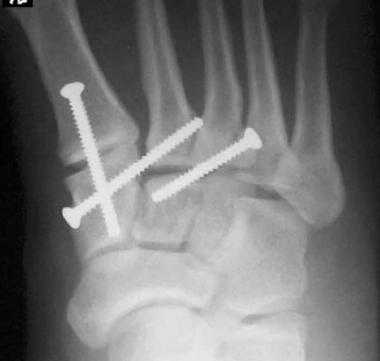

(Справа) При КТ в сагиттальной плоскости визуализируется вывих 5-й плюсневой кости в сторону подошвы. Необычная травма была получена при езде на велосипеде. (Слева) При рентгенографии среднего отдела стопы в передне-задней проекции определяется односторонний вывих сустава Лисфранка: 1-5 плюсневые кости смещены латерально, переломы не выявляются.

(Справа) Этому же пациенту были выполнены открытая репозиция и внутренний остеосинтез. При рентгенографии среднего отдела стопы в передне-задней проекции видно, что для обеспечения стабильности суставов требуется фиксация множества костей. Следует отметить наличие винта, который выполняет функцию поврежденной связки Лисфранка.

На данной рентгенограмме представлено очень серьезное повреждение стопы, возникшее следствие высокоэнергетической травмы. Результатом травмы стал вывих в суставах среднего отдела стопы).

Рентгенограмма стопы после лечения

Операция может быть рекомендована при любых повреждениях, сопровождающихся переломами костей среднего отдела стопы или изменениями анатомии (подвывихами) образующих его суставов. В задачи оперативного лечения входят репозиция костных фрагментов и восстановление анатомии суставов стопы.

Внутренняя фиксация. Данная операция заключается в восстановлении нормального положения (репозиции) костных фрагментов и фиксации их пластинками или винтами. Поскольку пластины и винты будут фиксировать и суставы, в которых норме существует небольшая подвижность, некоторые из этих металлоконструкций в последующем необходимо удалить. Сроки удаления конструкций в зависимости от решения хирурга могут варьировать от 3 до 5 месяцев после первой операции.

При смещении более 2 мм, нестабильности при функциональных тестах – рекомендовано открытое устранение вывиха с жёсткой фиксацией винтами или пластинами. Используются один или два продольных доступа в 1 и 2 межплюсневых промежутках. После обнажения первого предплюсне-плюсневого сустава первым этапом устраняется межклиновидная нестабильность, вторым этапом устраняется предплюсне-плюсневая нестабильность. В послеоперационном периоде сразу начинается разработка активного объёма движений. Нагрузку на стопу начинают постепенно, с тем чтобы полностью её восстановить к 6-8 неделе. Удаление спиц Киршнера производится через 6-8 недель, компрессирующих винтов через 3-6 месяцев. Возвращение к полной физической активности не ранее 9-12 месяцев после операции.

Открытое вправление вывиха, трансартикулярная фиксация 1-2-3 предплюсне-плюсневых суставов винтами.